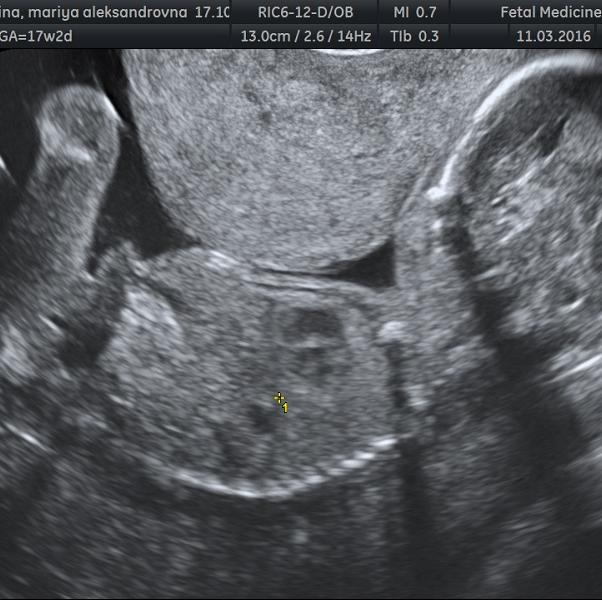

196 гр мальчика 😊

17 +2 💕

@bydy_mamoi07 @chalikushu @kabassya нет про тонус не говорили, плацента левая боковая, степень зрелости 0

@chalikushu, мне кажется это тонус 😬

@bydy_mamoi07, @kabassya я тоже заметила, но это может быть плацента

А про тонус вам ничего не говорили?

Где лицо и тело малыша его прижимает стенка матки. Это и есть тонус. Из за него движения ребёночка становятся ограниченными. Его обязательно надо снимать. Для начала магнеВ6 форте и свечи бускопан на ночь.